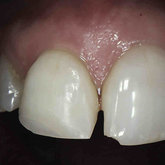

Porcelain crowns and restorations made in one appointment.

We make it a priority to incorporate the latest in dental technology in everything we do at our practice. ...